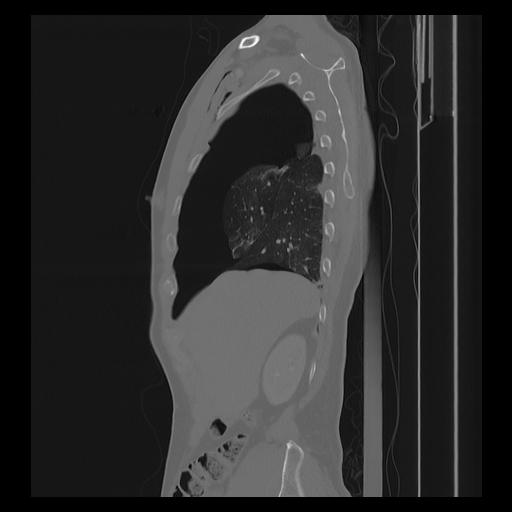

33 PULMON,CE,Sagittal,3.000,PULMON,Sagittal,